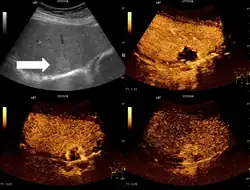

In den meisten Fällen werden Leberhämangiome im Rahmen einer Abdomensonographie diagnostiziert, oft als Zufallsbefund. Sie stellen sich dort als rundliche bis ovale, scharf begrenzte, echoreiche Strukturen dar. In der Duplexsonographie kann mitunter ein zuführendes Gefäß dargestellt werden.[1] Eine sichere Diagnose kann mittels Kontrastmittelsonographie erreicht werden: hier zeigt sich eine zentripetale Füllung (von außen nach innen) des Hämangioms mit Kontrastmittel.[2] Im deutschen Sprachraum wird dies auch als Irisblendenphänomen bezeichnet. Ebenso ist eine Diagnose mittels CT oder MRT möglich.